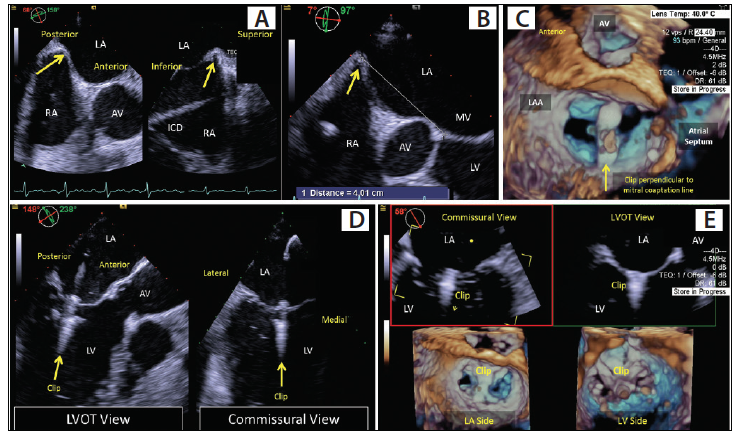

MitraClip (Abbott Structural Heart) is the only FDA-approved device for the treatment of native and, recently, functional MR.3 More than 80,000 MitraClips have been implanted worldwide,4 and thus, this article mainly focuses on the use of echocardiography during a MitraClip procedure. The first task is a comprehensive preprocedural assessment, which involves establishing the diagnosis, MR severity, and anatomic suitability for MitraClip repair (Table 1). Then, sonographers should follow mandatory steps to provide echocardiographic guidance during the procedure. The main steps for the MitraClip procedure include: (1) perform transseptal puncture; (2) introduce the guide catheter and clip delivery system into the left atrium (LA); (3) position the MitraClip above the mitral valve; (4) advance the MitraClip into the left ventricle (LV); and (5) grasp the mitral leaflet and deploy the MitraClip. The role of echocardiographic guidance for each step is presented in Table 2 and Figure 2.

Figure 2. Stepwise intraprocedural imaging of the MitraClip procedure for MR. TEE guidance of transseptal puncture in the superior and posterior aspect of the interatrial septum (A, B). Biplane 3D TEE image with septal tenting (A). Measurement of septal tenting from the plane of the mitral annulus (B). Three-dimensional TEE guidance of clip orientation perpendicular to the mitral coaptation line on the atrial side of the valve (C). Three-dimensional TEE biplane guidance of leaflet grasping by the clip on the ventricular side of the valve (D). The final result with a single clip deployed across the A2-P2 coaptation line (E). Reproduced with permission from the American College of Cardiology. Alter E, Jilaihawi H, Williams M, Saric M. Imaging in MV Interventions: MitraClip and Beyond… http://www.acc.org. Aug 06, 2018. Accessed May 14, 2019. https://www.acc.org/latest-in-cardiology/articles/2018/08/06/13/25/imaging-in-mv-interventions.